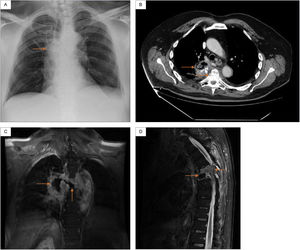

Physical examination was notable for crackles on auscultation in the upper and middle fields of the right lung, as well as spastic paraparesis with normal rectal tone. Blood test showed increased C-reactive protein 15mg/dL (reference range 0.5–1). Chest X-ray showed right paratracheal infiltrates (Fig. 1A). Chest CT showed cavitating right lung consolidation and crush located at T5-T6 (Fig. 1B). Thoracic spine MRI showed lung-spinal fistula and signs suggestive of spondylodiscitis (Fig. 1C and D).

(A) Chest X-ray: right paratracheal infiltrates. (B) Chest CT: right lung consolidation occupying the azygo-esophageal recess, with aire-fluid level and calcium deposits, as well as a marked crush and destructuring located at the T5-T6. (C) Thoracic spine MRI (coronal): central necrotic-cystic zone occupyping the disc space of the T5-T6 and fistulous communication with the adjacent right lung injury. (D) Thoracic spine MRI (sagittal): diffuse gadolinium enhancement and kyphotic deformity with canal stenosis located at the T5-T6.